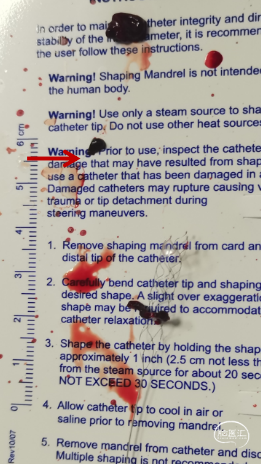

抽吸状态下整体撤出保护伞,继续抽吸,血栓堵塞SKATHI导管及导引导管,负压下整体将系统撤出,可见大量血栓。